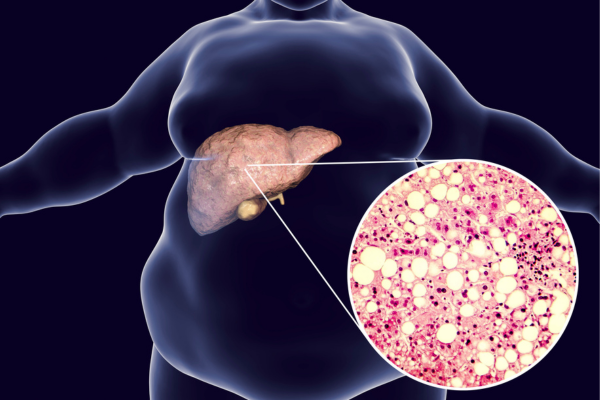

Gan nhiễm mỡ là tình trạng trong đó có sự tích tụ quá mức của mỡ trong các tế bào gan. Điều này có thể dẫn đến viêm gan, tổn thương tế bào gan, và nếu không được điều trị. Lâu dần có thể phát triển thành bệnh gan mãn tính hoặc xơ gan.

Có hai loại gan nhiễm mỡ chính:

1. Gan nhiễm mỡ không do rượu (NAFLD): Đây là dạng phổ biến nhất. Bệnh thường liên quan đến các yếu tố nguy cơ như béo phì, tiểu đường loại 2, rối loạn lipid máu, và hội chứng chuyển hóa. NAFLD không liên quan đến việc tiêu thụ rượu.

2. Gan nhiễm mỡ do rượu (AFLD): Xảy ra khi tiêu thụ rượu quá mức và kéo dài. Rượu có thể gây ra sự tích tụ mỡ trong gan, làm tăng nguy cơ viêm gan và xơ gan.

Các triệu chứng của gan nhiễm mỡ có thể không rõ ràng. Ở một số người có thể cảm thấy mệt mỏi, đau bụng trên bên phải. Có thể phát hiện bệnh qua các xét nghiệm hình ảnh hoặc xét nghiệm máu. Điều trị thường tập trung vào việc thay đổi lối sống, bao gồm giảm cân, cải thiện chế độ ăn uống, tăng cường hoạt động thể chất và kiểm soát các tình trạng bệnh lý liên quan.